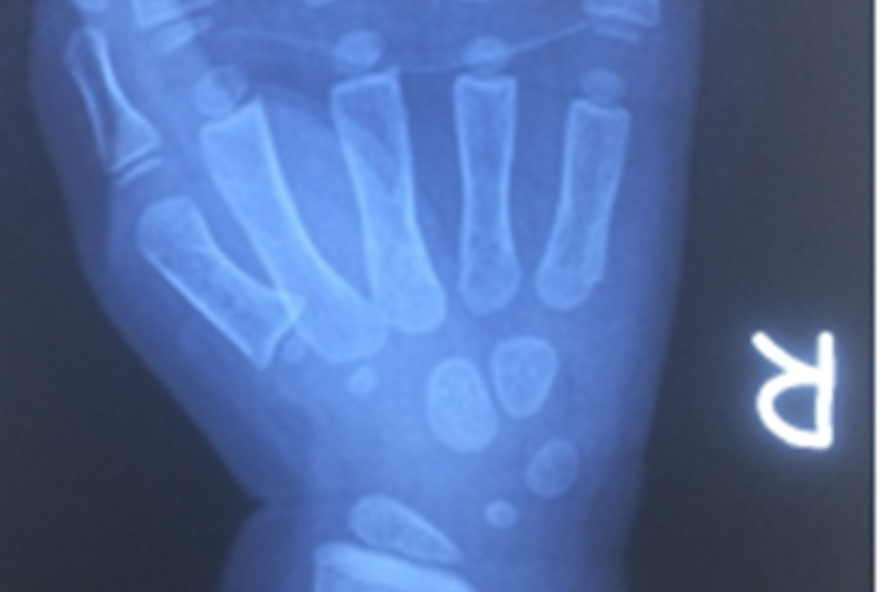

Phim chụp X-quang cho thấy tình trạng nguy kịch của đứa trẻ 2 tuổi. |

Con nát tay vì máy rửa xe máyBáo lao động đưa tin, bệnh nhi V.T.H.V (23 tháng tuổi, Sông Lô, Vĩnh Phúc) vừa được chuyển đến bệnh viện Hữu nghị Việt Đức trong tình trạng vết thương mặt mu ngón từ 1-5, đứt gân duỗi 2 tầng ngón 2,3,4, đứt gần rời ngón 5 tại vị trí khớp liên đốt gần. Bàn tay bé có nhiều vết bẩn dầu luyn.

Bác sĩ Nguyễn Hoàng Quân – Khoa phẫu thuật Chi trên và Y học thể thao, người trực tiếp mổ cho bé V cho biết đây là ca mổ của bệnh nhi nhỏ tuổi, các bác sĩ đã tập trung cẩn thận và tỉ mỉ vi phẫu, tiến hành bảo tồn ngón 5, khâu nối gân gấp ngón 5, khâu nối gân duỗi ngón ngón 2,3,4 và nẹp bột cẳng bàn tay. Hậu phẫu ngày thứ 2, các ngón của người bệnh đầu chi ấm nhưng vẫn cần theo dõi thêm.